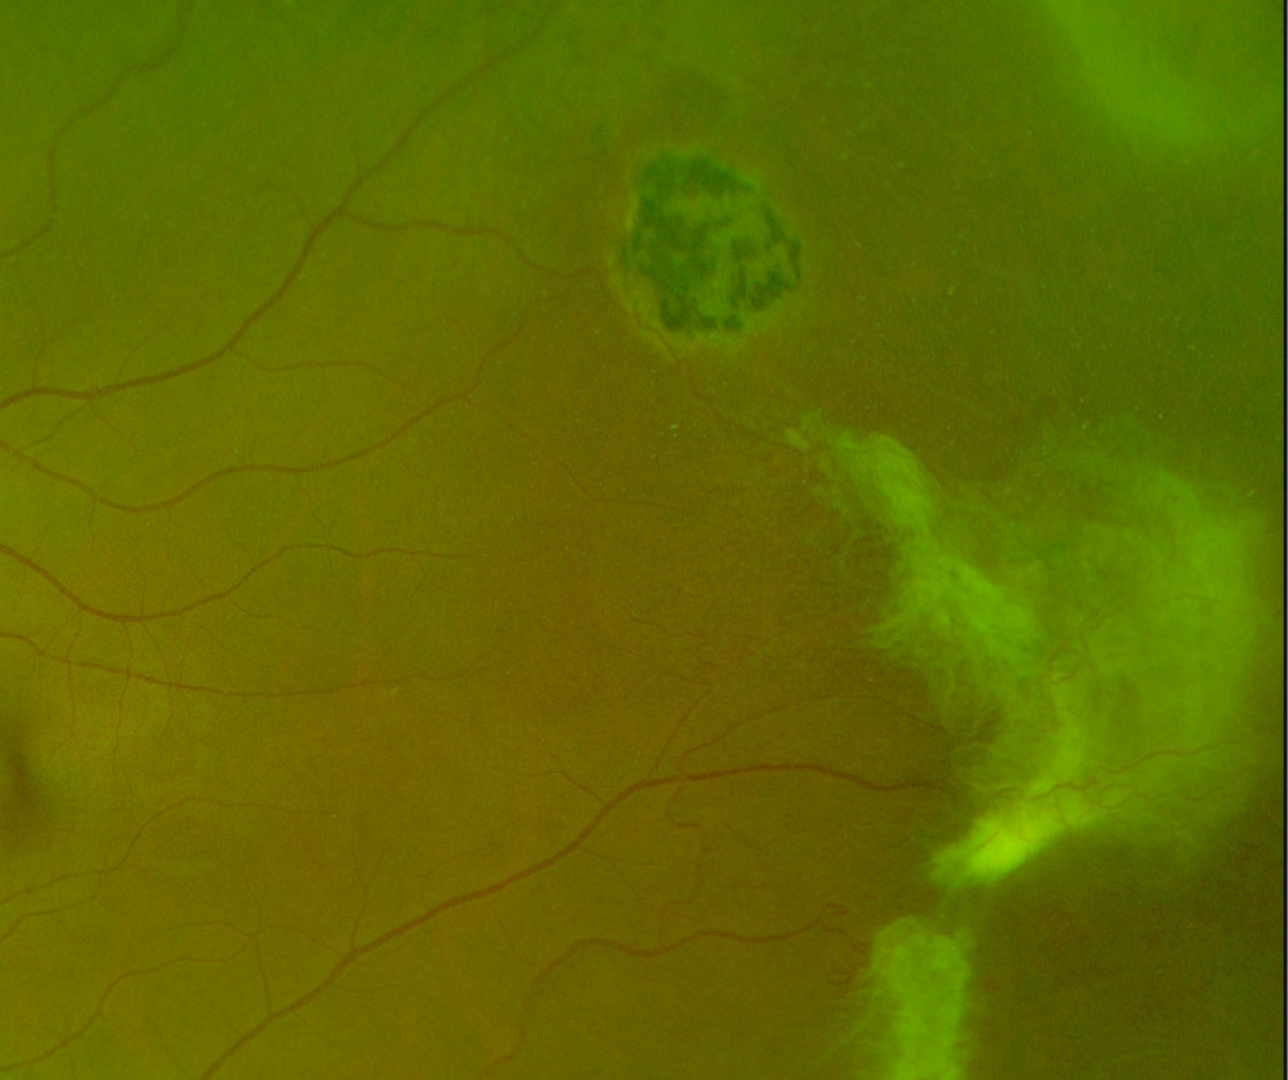

Sunburst lesions are localized areas of retinal pigment hypertrophy, hyperplasia and pigment migration as seen in the OCT. The lesions often appear speculated and are typically found in the peripheral retina in a perivascular location. The ”sunburst” lesions usually form secondary to reabsorbed sub-retinal haemorrhages and appear on fundus autofluorescence as an area of hypo-autofluorescence with a hyper-autofluorescent border. They are characteristic of sickle-cell retinopathy.

This patient also has a second characteristic feature of sickle cell retinopathy – pre-retinal “sea fan” neovascularization. This typically occurs in sickle-cell patients at the posterior border of an area of retinal non-perfusion, and can lead to vitreous haemorrhage and eventually tractional retinal detachment.

More infoOptomap green separation image (right eye)